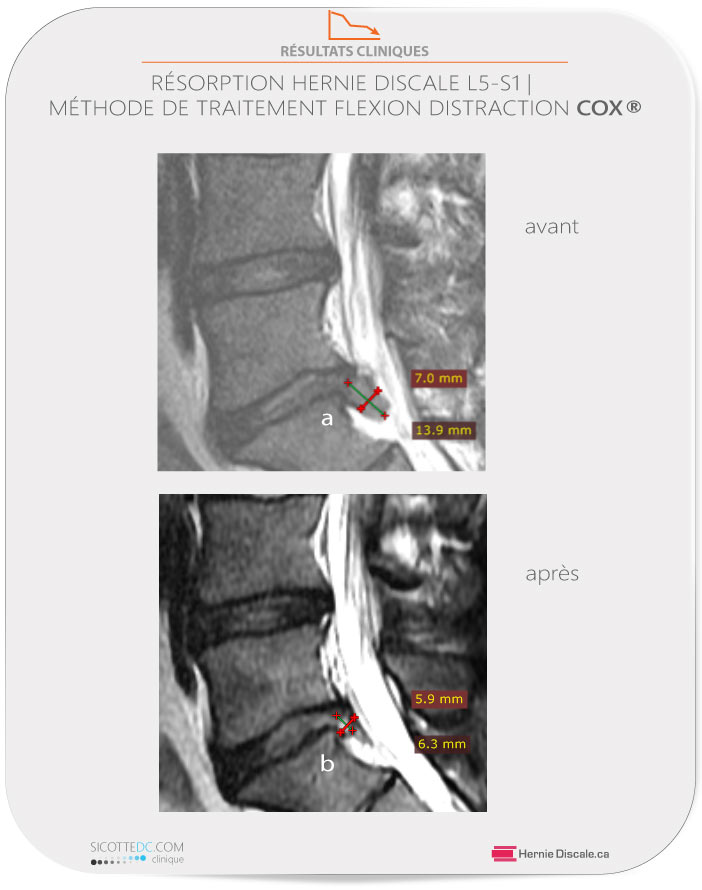

RÉSORPTION D’UNE HERNIE DISCALE AVEC TRAITEMENT MÉTHODE COX®

Référé à notre clinique par sa conjointe il avait été examiné par d’autres cliniciens qui n’ont toutefois pas perçu les signes de lésion discale. Le patient était antalgique (posture modifiée en raison de la douleur) et avait une douleur située à 7/10. L’examen physique démontre la suspicion d’une sciatalgie (fort probablement à cause d’une hernie discale). Une IRM est prescrite et vingt-quatre heures plus tard, le patient revient à notre clinique pour débuter ses soins. Après 12 semaines de soins continus, le patient retrouve une vie normale.

b : Trois mois après le dernier soin de distraction Cox®, la lésion a subi une résorption importante pour atteindre 5,9 mm x 6,3 mm. Une diminution de volume, sur le plan sagittal, de 61%.